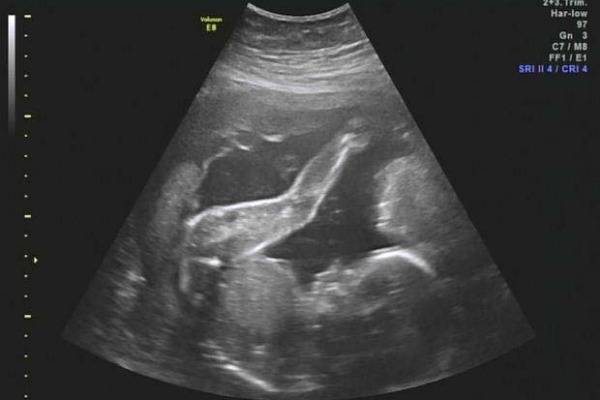

На втором УЗИ (20–22-я недели) исследуются следующие показатели ребенка и матери:

- Биометрия плода. Если показатели ниже нормы, возможна задержка развития. Однако при незначительных отклонениях волноваться не стоит.

- Патологии плода на УЗИ лучше всего заметны именно на этом сроке. Для исключения вероятных проблем проверяется наличие формирующихся органов, ручек и ножек. Часто на этом сроке заметен даже пол ребенка. Отсутствие любой части тела свидетельствует о врожденных аномалиях.